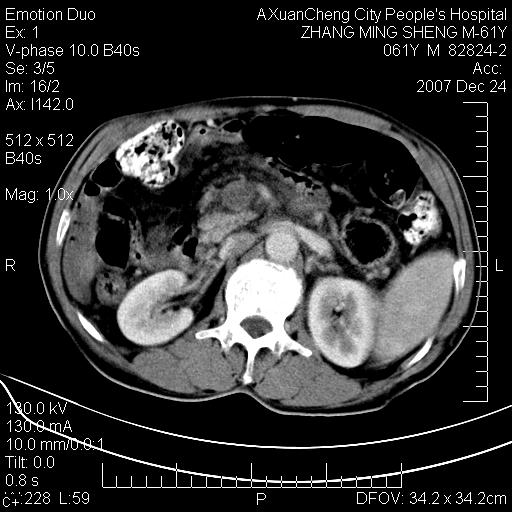

标题: CT11031:M61Y,胰腺占位

大家侃侃门静脉和胆管系统怎么回事,肝内转移?

1,肝硬化,脾大.

2,肝内多发结节状低密度占位,伴门脉及肠系膜上v栓子形成.考虑a;门脉及肠系膜上v血栓后肝改变.b;弥漫型肝癌伴门脉及肠系膜癌栓.

肝硬化,门脉高压,脾肿大;弥漫性肝癌,肝内、门脉、腹膜后淋巴结转移,肝内外胆管扩张,胰头区占位,建议mr检查

考虑为:胰腺癌伴肝脏转移、腹膜后淋巴结转移,门静脉及肠系膜上静脉瘤栓形成。

肝硬化,脾大. 胰腺癌伴肝内转移;门脉、肠系膜上v癌栓形成。